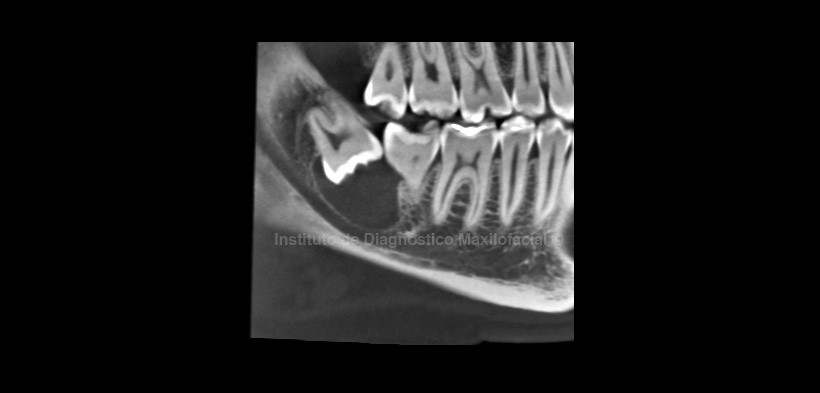

En la radiografía panorámica (Fig 1) se observa una imagen radiolúcida unilocular de limites definidos y corticalizados, asociada a la corona de la pieza 4.8 sugerente de Quiste Dentígero.